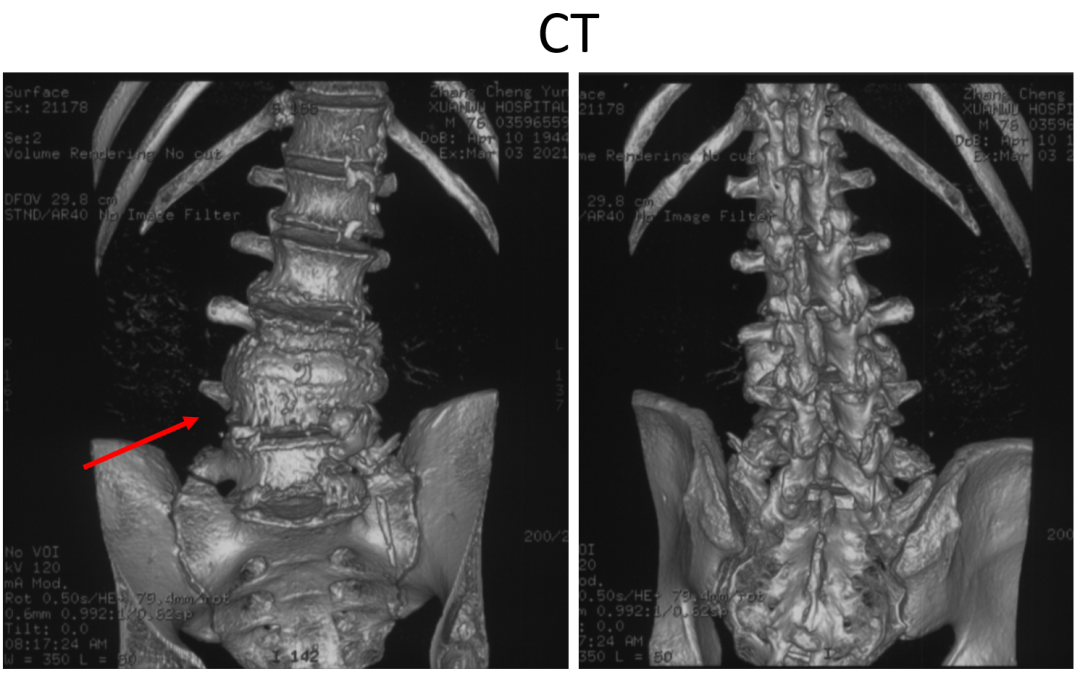

讨论主题:L4压缩骨折伴脊柱侧后凸畸形

影像资料:

腰椎侧后凸畸形

腰椎陈旧性压缩性骨折(L4)